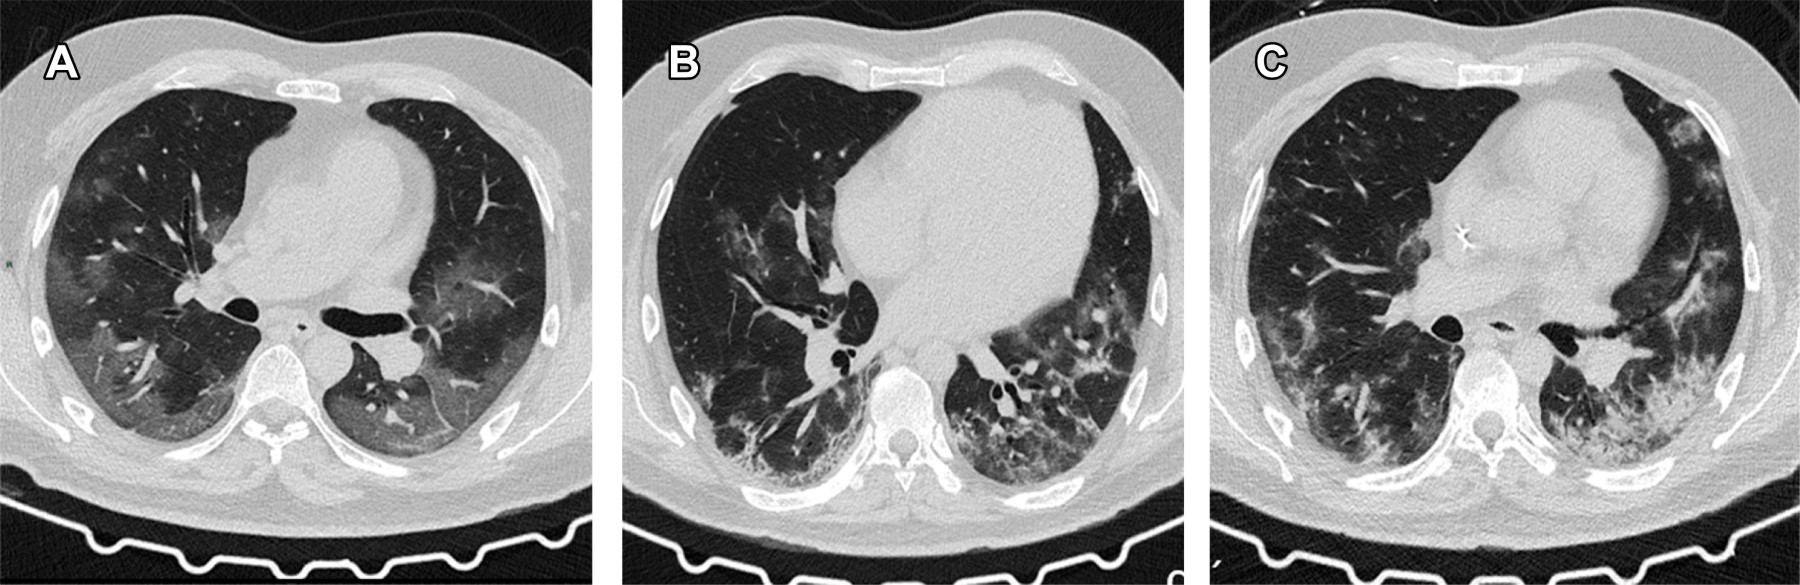

Los hallazgos tomográficos principales de COVID-19 son la presencia de imágenes en vidrio despulido bilaterales y de distribución periférica, que se describen como opacidades pulmonares que no oscurecen los márgenes vasculares o bronquiales subyacentes, están relacionados con afectación del espacio aéreo y engrosamiento intersticial; a medida que avanza la enfermedad, el número de lesiones puede aumentar rápidamente. Las consolidaciones son secundarias al reemplazo completo de espacios aéreos alveolares por fluidos patológicos que llevan a un aumento en la densidad parenquimatosa, oscurece los vasos subyacentes y paredes bronquiales. El patrón en "empedrado" o "adoquinado" (crazy paving pattern) se define como la presencia de vidrio despulido con engrosamiento septal interlobulillar superpuesto que da la apariencia de adoquines irregulares.5 Las linfadenopatías mediastinales son hallazgos que no están reportados de forma frecuente en la literatura y se definen como un ganglio linfático cuyo diámetro en el eje corto es mayor a un centímetro a este nivel. Entre otros hallazgos descritos se encuentran las bronquioloectasias, atelectasias, zonas de fibrosis y derrame pleural.6 Los principales hallazgos tomográficos en el presente estudio se detallan en la Figura 1.

Los hallazgos tomográficos comúnmente observados en pacientes con COVID-19 son la expresión del daño pulmonar intersticial agudo y cambios parenquimatosos resultantes del proceso inflamatorio que condicionan opacidades en vidrio despulido por afectación intersticial, en algunas ocasiones asociado a engrosamiento septal. Conforme avanza la enfermedad pulmonar se observan áreas de consolidación parenquimatosa como complicación, estos datos coinciden con los pacientes reportados en este artículo, donde el principal hallazgo tomográfico fue el vidrio despulido en la mayoría de los pacientes, seguido del patrón adoquinado (crazy paving) y áreas de consolidación.11

Los hallazgos tomográficos principales en pacientes con sospecha de enfermedad COVID-19 y prueba RT-PCR negativa fueron las opacidades en vidrio despulido, seguidas de un patrón adoquinado y consolidaciones pulmonares, lo cual tiene relación con los hallazgos encontrados y basados en la escala CO-RADS, en donde se observa una clasificación 5 en su mayoría con alta sospecha de la enfermedad en pacientes con datos clínicos y prueba confirmatoria RT-PCR negativa, por lo que podrá orientar, en casos dudosos, el inicio del tratamiento y aislamiento de los pacientes para un adecuado control de la enfermedad.